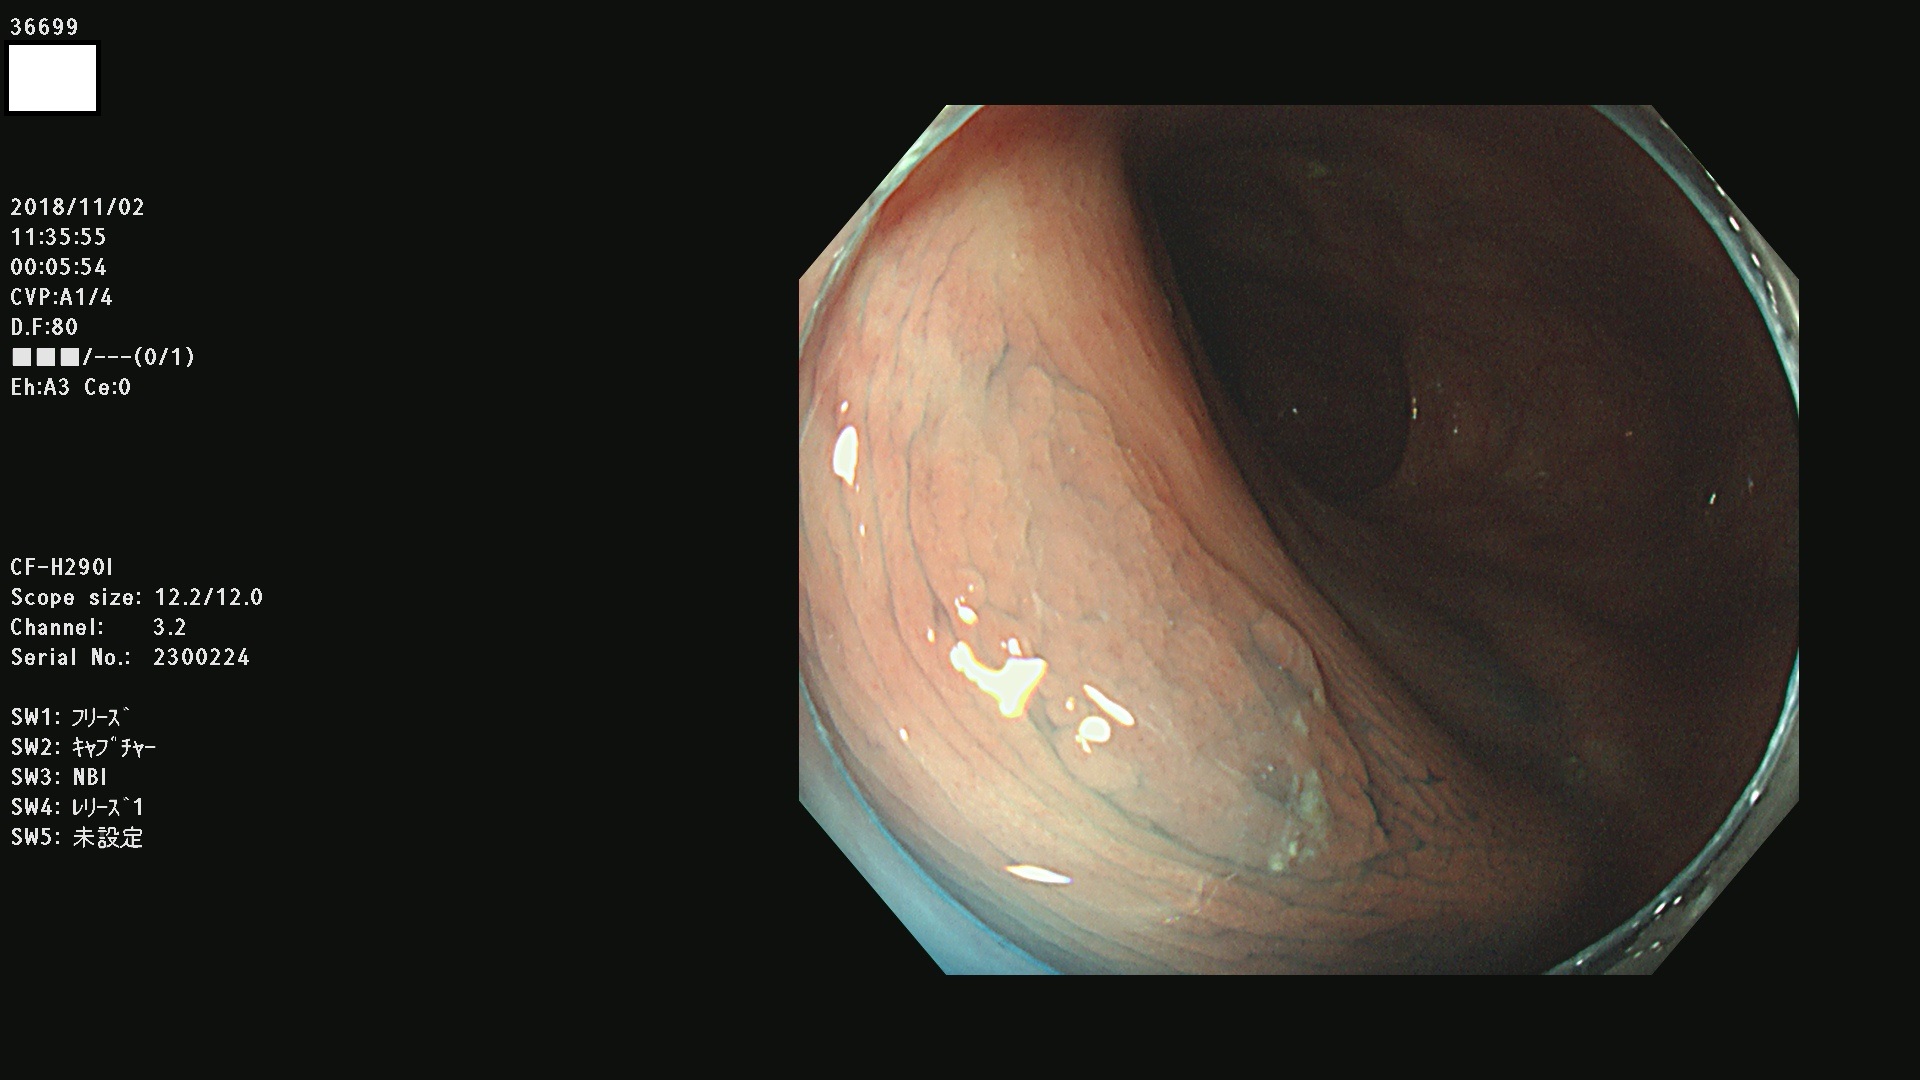

36600 36601 36603 36605 36606 36608 36609 36610 36611 36612 36613 36615 36617 36620 36621 36624 36625 36626 36627 36628 36629 36631(SSAPのみ) 36632 36633 36634 36636(SSAPのみ) 36637(SSAPのみ) 36639 36640 36642 36643 36644 36646 36647 36648 36649(SSAPのみ) 36650(SSAPのみ) 36652 36653 36654 36655(SSAPのみ) 36656 36657 36658 36659 36660 36661(SSAPのみ) 36665 36668 36669 36672 36673 36676 36677 36678 36679 36681 36682 36683 36684 36685 36687(SSAPのみ) 36691 36692 36693 36694 36695 36696 36697 36699(SSAPのみ)